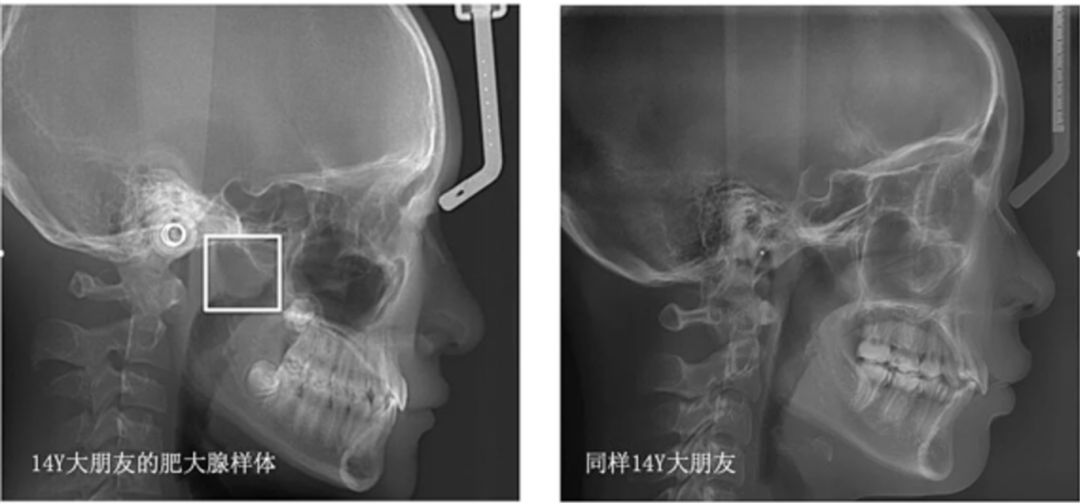

在孩子的成长过程中,家长们总是关注他们的身体健康和发育状况。然而,有一种常见的问题——腺样体肥大,却往往被忽视。它不仅影响着孩子们的呼吸、睡眠质量,还可能导致面部发育异常,形成所谓的“腺样体面容”。今天我将从腺样体面容开始详细讲解这一疾病,让家长重新了解腺样体肥大。首先介绍一下家长最担心出现的腺样体面容,但是什么样的面容才是腺样体面容呢?这种面容表现为上颌骨变长,下颌骨后缩,腭盖高拱,牙列不齐,上切牙突出,嘴唇变厚,缺乏面部表情,面容呆滞,看起来有点呆傻,故也可以称为"痴呆面容"。

腺样体位于鼻咽顶壁和后壁的交界处,双侧咽隐窝之间,过度肥大会影响鼻部通气功能,从而造成儿童长期口呼吸,进一步造成儿童面骨发育异常。但是出现上颌骨变长不一定是腺样体肥大,家长们往往忽视遗传的作用,和儿童自身的习惯性口呼吸。